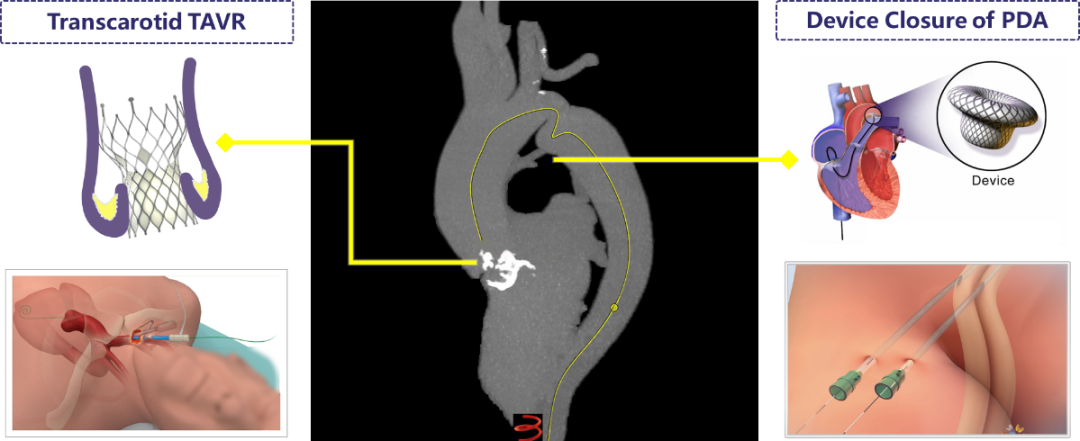

近日,吉林大学第二医院刘斌主任、张春鹏教授带领TAVR团队,成功实施一站式TC-TAVR+PDA封堵手术,成功救治一位重度主动脉瓣狭窄合并主动脉缩窄、动脉导管未闭的患者,该一站式手术为东北首例。

面对复杂严重的病情,团队术前经过细致的评估,制定了详细的手术计划,通过介入疗法,一站式实施动脉导管未闭介入封堵术及TAVR手术。术后1天患者自述症状明显缓解,随访情况良好。

主动脉缩窄多为先天发育异常导致的,手术治疗的最佳年龄是6-16岁,由于成人后血管脆性增加,手术较为困难,故此次术中未进行干预,术后测量上肢血压:132/77 mmHG,下肢血压:177/95 mmHG,提示患者主动脉缩窄并未影响血流动力学;PDA封堵器位置良好,未见残余分流;人工主动脉瓣膜位置形态良好,跨瓣压差由49 mmHG降至8 mmHG,微量瓣周漏;手术取得圆满成功。